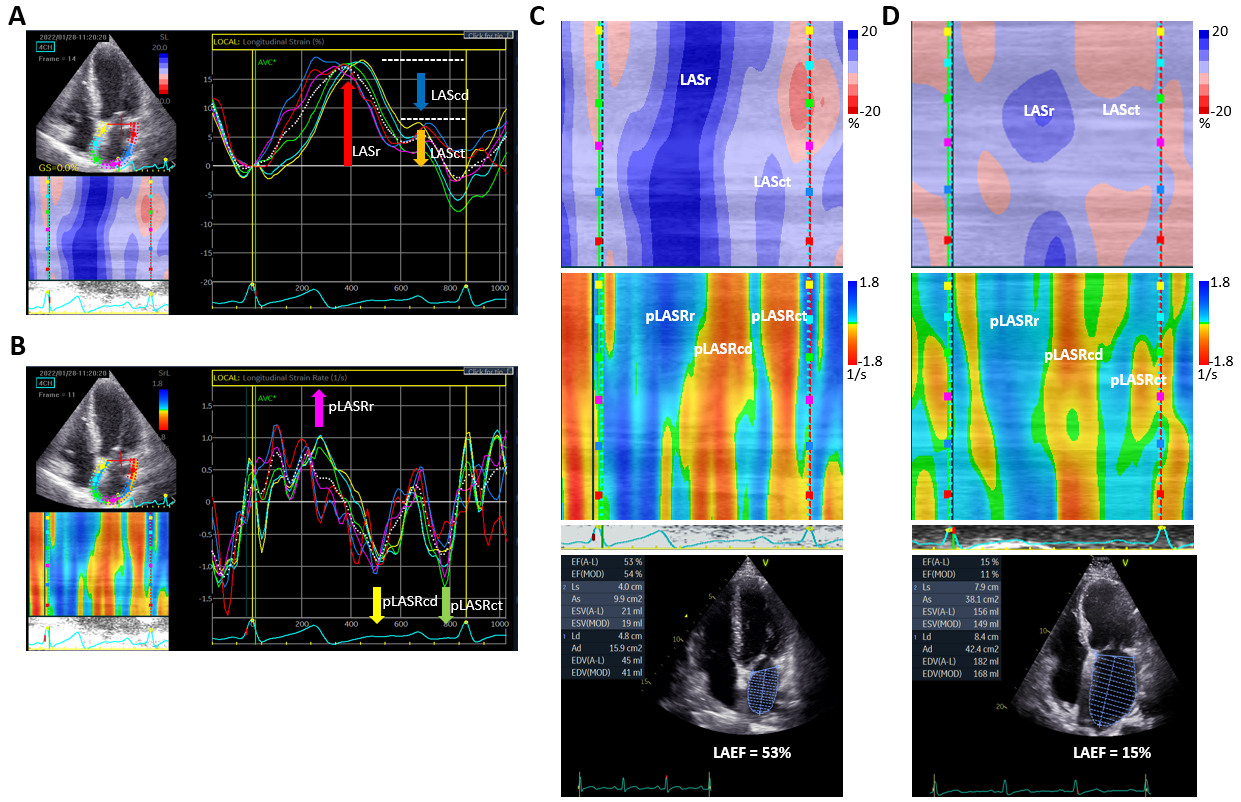

Speckle-tracking echocardiography (STE) is a novel, non-Doppler echocardiographic method to measure the magnitude and rate of atrial myocardial deformation by calculating the longitudinal strain and strain rate independent of cardiac rotational motion and the tethering effect [90, 91]. Strain is a dimensionless index that reflects total deformation of the myocardium relative to its initial length during the cardiac cycle [92], expressed as a positive value for lengthening or a negative value for shortening. STE tracks the natural acoustic markers within a region of interest (kernel) frame-by-frame, evaluating the geometric shift of each kernel throughout the cardiac cycle [36]. Fig. 1A shows an example of LA strain via the apical 4-chamber view. LA strain reaches its maximal value just before the mitral valve opening, and LA strain during the reservoir phase (LASr) is measured as the strain value at the mitral valve opening minus that at the ventricular end-diastole (a positive wave occurring during the ventricular systole) [90]. When the LA conduit phase begins, LA volume gradually decreases to a plateau until the 2nd late peak, just before the onset of the active atrial contractile phase. The strain value at the onset of atrial contraction minus that during the mitral valve opening is a surrogate of LA strain at the conduit phase (LAScd). The strain value at the ventricular end diastole minus that during the onset of atrial contraction is a surrogate of LA strain at the contraction phase (LASct). Strain rate is the rate by which the deformation occurs. Fig. 1B shows an example of LA strain rate. There is one positive peak during the reservoir phase (pLASRr) and two consecutive negative peaks during the LV diastolic phase. The first peak represents passive myocardium shortening (pLASRcd) and the second peak is the minimal value after the LA active pump phase (pLASRct). The assessment of LA strain and strain rate can use a 4-chamber view or both 4- and 2-chamber views to report the average values from 6 or 12 segments, respectively [90].

Fig. 1.Transthoracic echocardiography in the apical four-chamber view

showing left atrial (LA) longitudinal strain and strain rate. (A) LA strain in a

paroxysmal atrial fibrillation (PAF) patient 1-day post ablation. Taking the R

wave as the starting point, the first positive peak corresponds to the LA

reservoir phase (LASr) (red arrow), the second peak corresponds to the LA

contractile phase (LASct) (orange arrow), and the difference between the two

peaks corresponds to the conduit phase (LAScd) (blue arrow). The traces are

time–displacement displays, with the x-axis representing time and the y-axis

showing myocardial shortening as negative and lengthening as positive (%). The

depicted LA wall is divided into six segments marked by different colors. (B) The

LA longitudinal strain rate in the same patient as in panel (A). The traces are

time-velocity displays, with the x-axis representing time and the y-axis

representing velocity (s